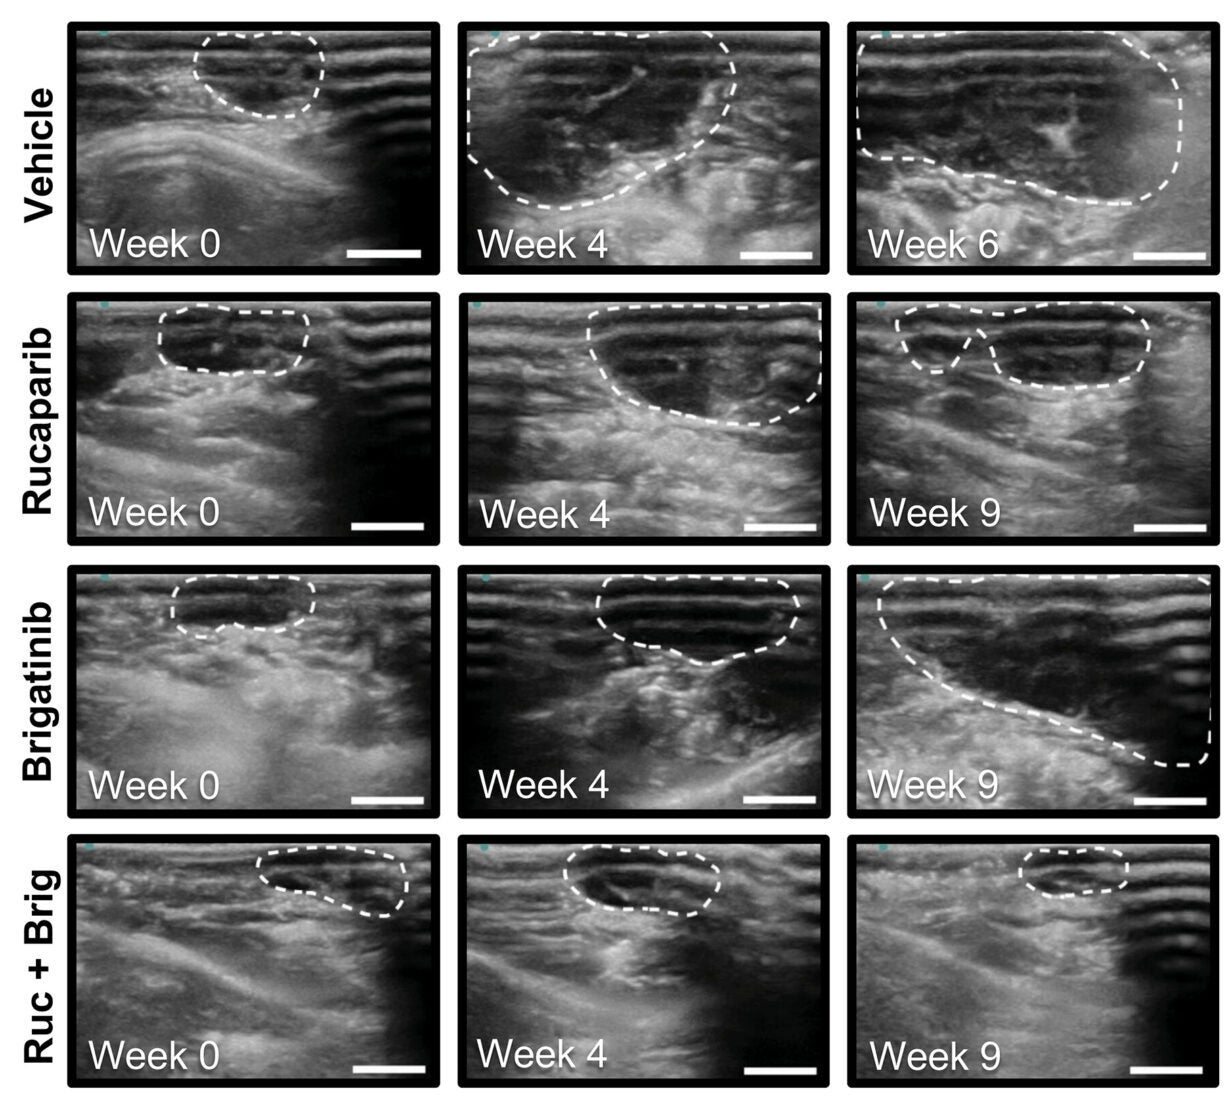

![Representative ultrasound images of intraperitoneal tumors in PH747 mice [shown in (A)] at the indicated time points and treatments. White dashed lines outline tumor area.](https://www.thebrighterside.news/uploads/2026/02/Lung-cancer-drug-3-scaled-e1771275716579.jpg)

Laboratory data may not always translate to animal model systems that mimic patients with ovarian cancer. Therefore, the research group evaluated whether dual treatment was beneficial using patient-derived xenograft mouse models of ovarian cancer. Seven different ovarian cancer xenograft models representing many genetic backgrounds were examined, including those containing BRCA mutations or other DNA repair defects, as well as those that had developed resistance to PARP inhibitors.

Combination treatment with brigatinib and a PARP inhibitor produced a larger decrease in tumor size relative to each individual drug. Combination-treated mice survived longer than single-drug-treated mice. Combination treatment did not appear to be associated with significant toxicity in most mice across studies, except for rare episodes of excessive weight loss.